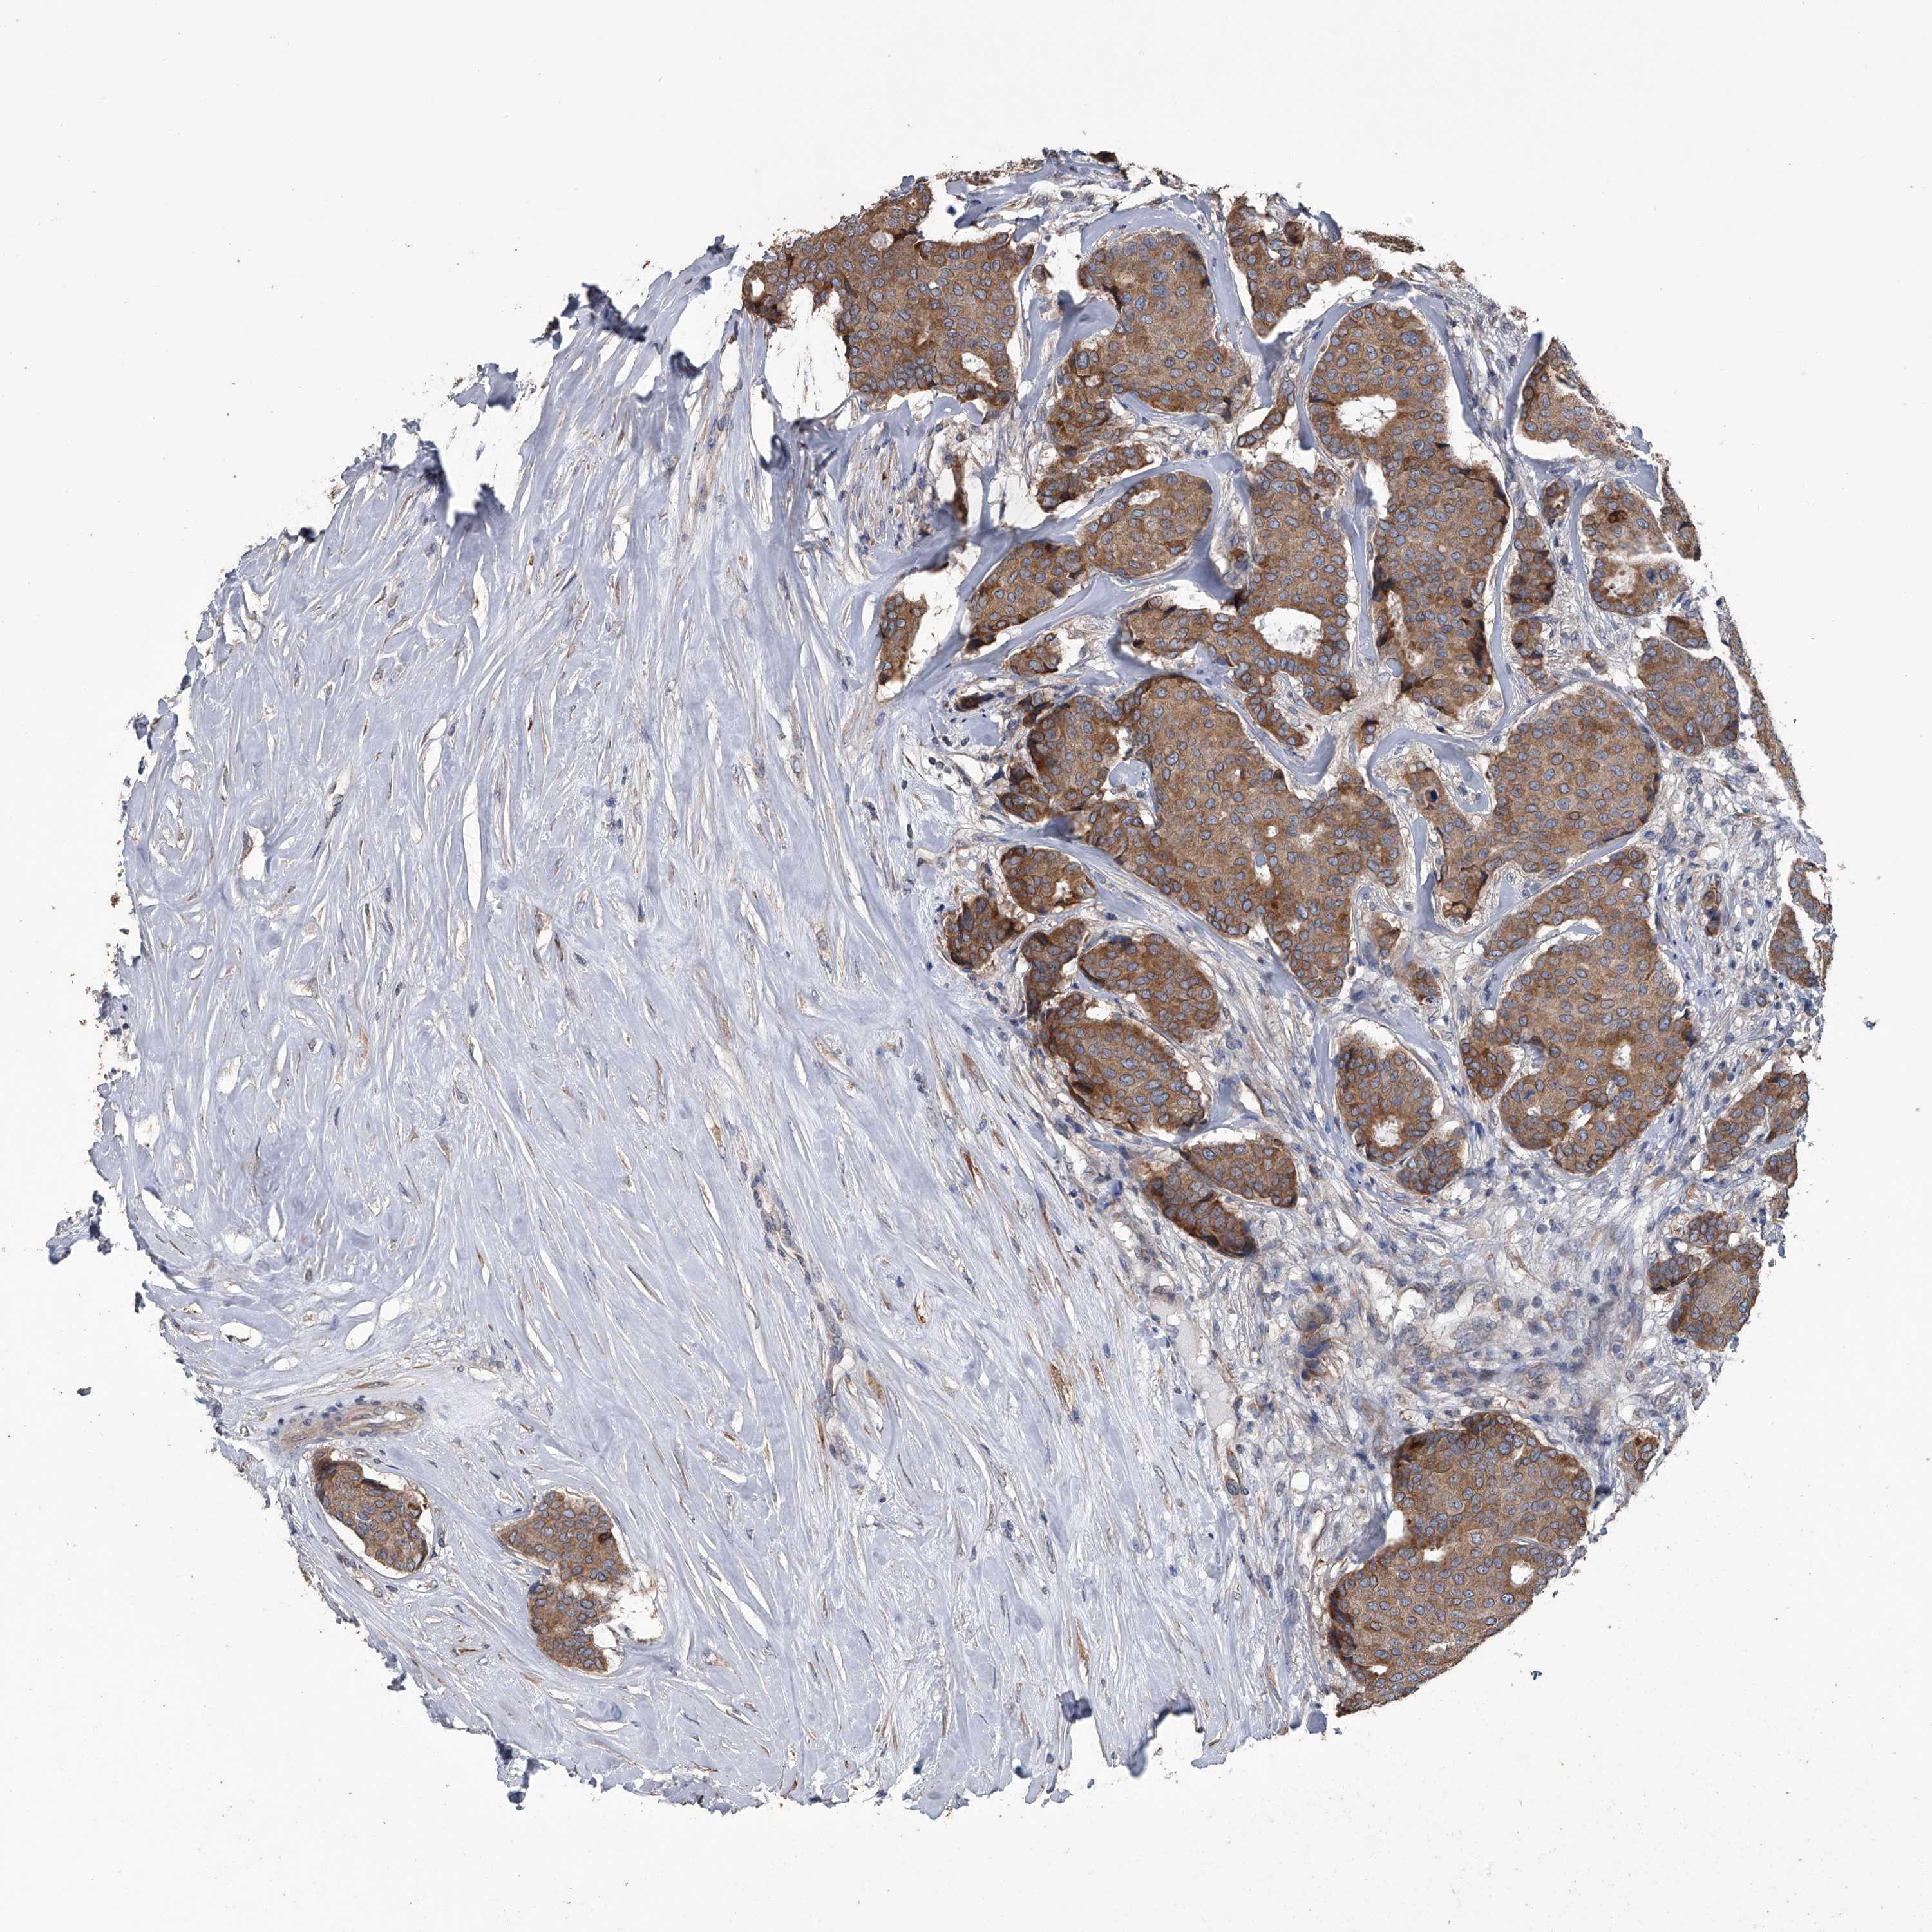

CANCER BREAST CANCER Show tissue menu

BRCA TCGA BRCA VALIDATION PROTEIN EXPRESSION